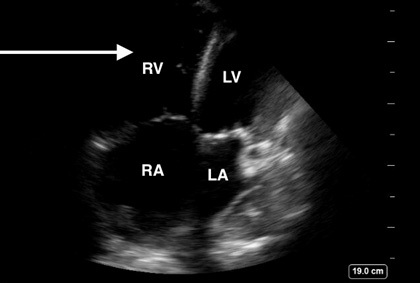

Figure 2. Right Ventricle Dilation Secondary to Increased Right-Sided Heart Pressures |

Point-of-care ultrasound image demonstrating an apical four chamber view with RV dilation (white arrow) secondary to increased right-sided heart pressures |